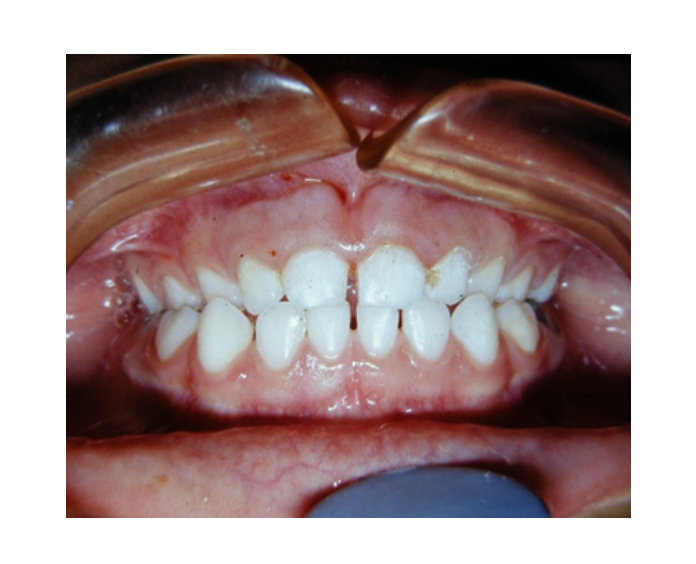

Clase I Protrusión

dental